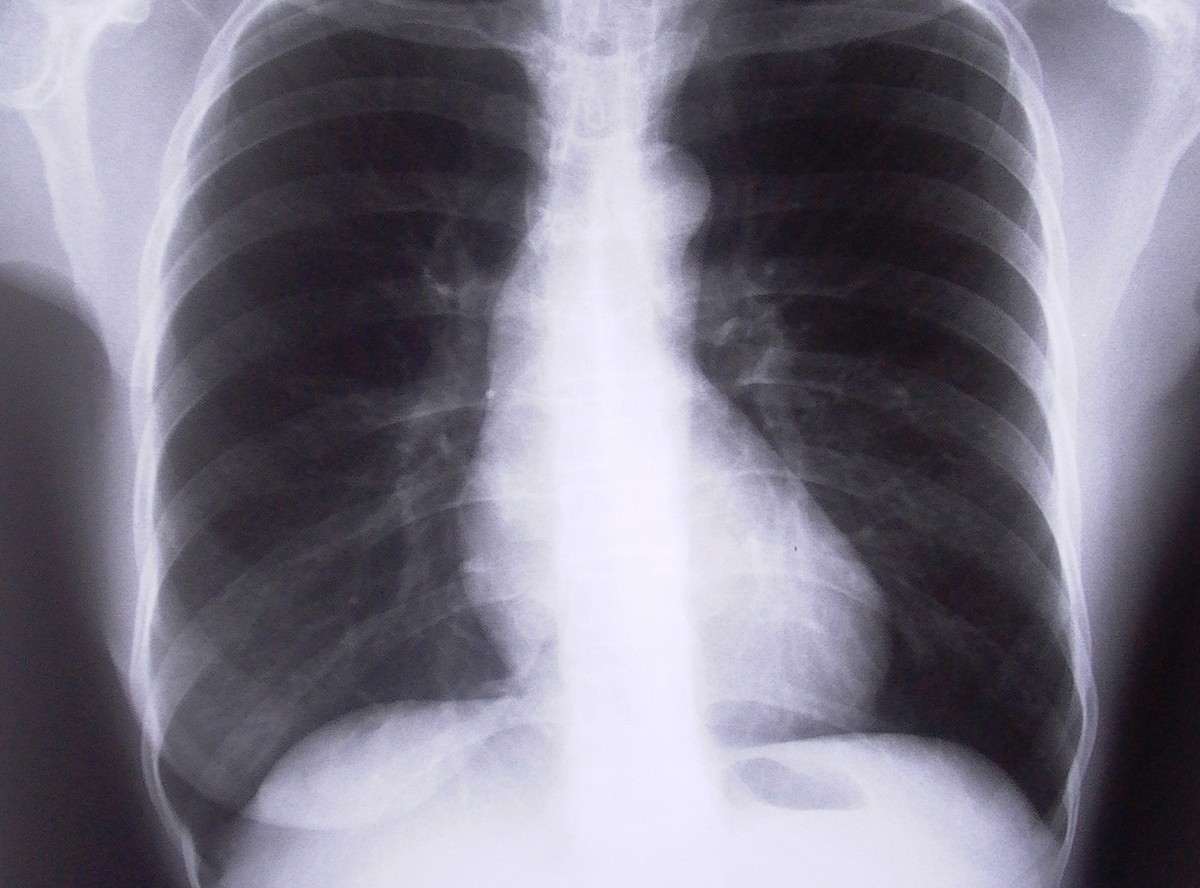

Na każde 100 tysięcy Polaków 330 zachoruje na nowotwór, a z chorych 240 umrze. Głównie na raka płuc - wynika z raportu przygotowanego przez Centrum Onkologii w Warszawie. Nowotwory złośliwe to druga przyczyna zgonów w Polsce, powodują ponad 26 procent zgonów u mężczyzn i 23 procent zgonów u kobiet.

U kobiet rak najczęściej atakuje piersi, płuca i szyjkę macicy. Rośnie zwłaszcza liczba zachorowań na raka płuc. Już w siedmiu województwach ten właśnie nowotwór jest pierwszą przyczyną śmiertelności spowodowanej rakiem. Nadal niekorzystnie wypadamy na tle Europy w walce z rakiem szyjki macicy. Tym bardziej że w Europie aż 80 procent pacjentek przeżywa z nim 5 i więcej lat. Natomiast umieralność z powodów raka żołądka u kobiet wykazuje systematyczny spadek.

U mężczyzn, u których w drugiej połowie XX wieku najszybciej rosło zagrożenie nowotworem płuc, w ostatnich dwóch dekadach ten wzrost został zahamowany i odwrócony - dzięki coraz mniejszej popularności palenia papierosów. Nadal jednak rak płuc odpowiada za największą zachorowalność, wyprzedzając raka jelita i raka prostaty.